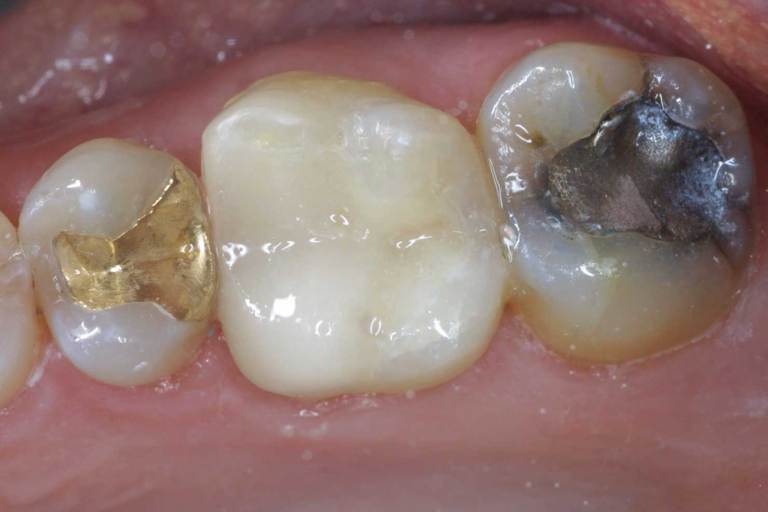

There are four different choices that you have when it comes to filling a cavity.

- Composite Fillings - Natural tooth-colored filling, bonds to the tooth to provide added security.

- Silver Fillings - Inexpensive and strong amalgam based filling.

- Gold Fillings - More attractive than silver and provide for a better fit.

- Porcelain Fillings - Also called inlays; the most attractive and durable of the tooth colored choices.